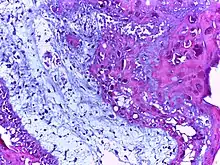

![]() | Squamous cell carcinoma of the skin | Well-differentiated squamous cell carcinoma skin showing malignant cells with mild atypia resembling normal squamous epithelial cells with intercellular bridges, individual cell keratinisation and nests of keratin pearls. | Category: Histopathology of squamous cell carcinoma of the skin | Squamous cell carcinoma |